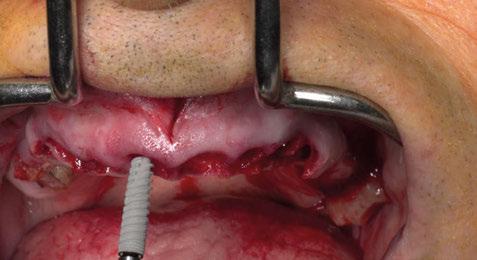

Figura 16. Caso clínico 3. a) situación clínica basal. b) situación clínica en revaluación tras terapia periodontal básica y extracción de un incisivo inferior. c) radiografía 2D inicial.

Figura 17. Procedimiento quirúrgico. a) extracción de incisivo central inferior y colgajo de acceso apical vestibular. b) posicionamiento ideal del injerto de tejido conectivo autólogo. c) sutura del injerto de tejido conectivo; d) utilización de aloinjerto particulado (OraGRAFT® Aloinjerto Cortical Particulado MIX 70% Mineralizado / 30% Desmineralizado) para reconstruir la dehiscencia ósea y preservar el alveolo resultante de las dos extracciones.

CASO CLÍNICO 3 (FIGURAS 16-23)

Se trata de un paciente de 57 años de edad que acude a la clínica con motivo de tener un complejo psicológico debido a la situación de sus incisivos inferiores. Presenta una reabsorción radicular en el diente en posición de 31, que además tiene una pérdida de inserción avanzada, al igual que los otros tres incisivos. Se realizó tratamiento periodontal

básico y la extracción del diente 31 previa a la cirugía. Procedemos a realizar el mismo colgajo de acceso apico-vestibular mencionado anteriormente. En este caso se extrae el diente en posición de 41 durante el procedimiento quirúrgico.

En este sentido, vuelve a realizarse el mismo protocolo de materiales que en el primer caso clínico. Es decir, en primer lugar se sutura un injerto de tejido conectivo al colgajo; posteriormente se utiliza un injerto óseo alogénico particulado (OraGRAFT® Aloinjerto Cortical Particulado MIX 70% Mineralizado / 30% Desmineralizado) para reconstruir la dehiscencia ósea además de preservar el escaso alveolo del diente extraído; y adicionalmente se utiliza la lámina de cortical desmineralizada (Lámina de cortical desmineralizada Cortiflex® Salugraft Dental).